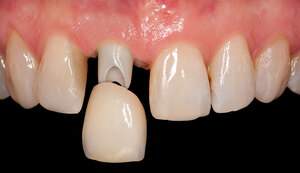

歯周病や歯の根の病気の影響で大きく骨が失われてしまうことが良くあります。これは同時に大きく歯茎も失われてしまうことを意味しています。

インプラント周囲の歯茎が薄いと機能的・審美的にも良好な状態を維持することが難しくなります。そのため長く良好な状態を保つためには歯茎の移植をする場合があります。

主に前歯の歯肉の移植です。

オペをすることで審美的、機能的にも良好な結果が得られます。

主に奥歯の歯肉の移植です。

オペをすることで特に機能的な良好な結果が得られます。